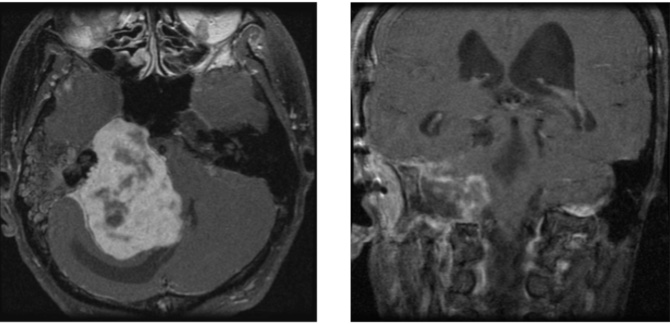

37歳男性 歩行障害、嚥下困難で発症 他院でサイバーナイフを推奨され当院に来院された。腫瘍が大きく、若年でもありまずは摘出を行い、残存部分に定位放射線治療を行う方針とした。下位脳神経(のどの筋肉を支配する神経)由来の神経鞘腫特殊な静脈構造をしており、後頭部を開放することが出来ず、全錐体アプローチにて摘出を行った。術後顔面麻痺が出現したが、歩行障害など改善し退院。

(左図)術前造影MRI

(右図)術後MRI 被膜のみを残して摘出